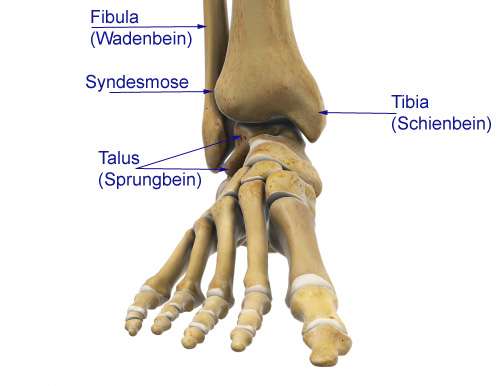

Impingement des oberen Sprunggelenks: Die knöchernen Anbauten am Schienbein (Tibia) und Sprungbein (Talus) führen zu einer Blockade des oberen Sprunggelenks (OSG). © Gelenk-Klinik

Anatomie des Sprunggelenks von vorne: Drei Knochen bilden das Sprunggelenk: Tibia (Schienbein) und Fibula (Wadenbein) gleiten über den Talus (Sprungbein). Jede schmerzhafte Einschränkung der Sprunggelenksbeweglichkeit vorne (anterior), hinten (posterior oder dorsal) oder seitlich (lateral) wird als Sprunggelenksimpingement bezeichnet. © Viewmedica